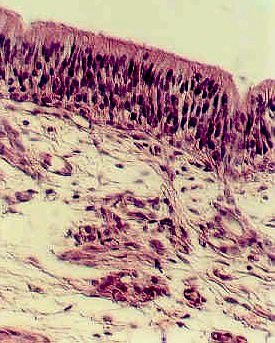

The nuclei nearest the lumen belong to the Sustentacular cells. They are elongated. The middle layer of nuclei are rounder and somewhat paler. These belong to the Olfactory cells. The nuclei of the Basal cells are the third layer, nearest the connective tissue. They may be difficult to identify. Study an electron micrograph of Olfactory cells and learn how they are specialized for olfactory sensation. Also, learn the function of each of these three cell types.

Underneath the epithelium is connective tissue called the Lamina Propria, which is loose connective tissue. You can identify glands which produce the fluid that dissolves substances to be smelled. These are called Bowman's glands. You can also see large nerve fiber bundles of Cranial Nerve I.called the Filia Olfactoria. These will synapse in the olfactory bulb.